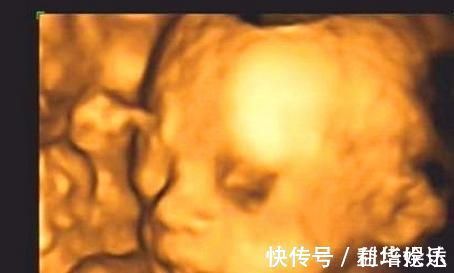

3.彩超中做鬼脸我们都知道,一般在准妈妈到了怀孕六个月左右的时候,就可以去医院里面做四维彩超这项检查了,通过四维彩超能够清楚的看到宝宝的模样以及宝宝的发育情况。如果准妈妈在做四维彩超的过程中,发现宝宝有稀奇古怪的表情时,这种现象是说明宝宝的大脑发育比较健全,点起来宝宝也是通过自己的这样的方式,间接的告诉着妈妈的心情如何,这种现象也是说明宝宝是个高智商的表现。